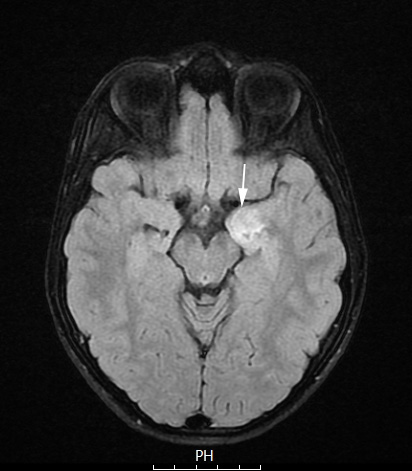

Case 3 History ---- The patient is an 11-year-old boy with alpha-gal syndrome who presented in August 2025 with headache, dizziness, fatigue, tinnitus, visual changes, light sensitivity, acute-on-chronic abdominal pain, weight loss, and difficulty swallowing liquids, and was incidentally found to have a small pituitary cyst and a left medial temporal lesion on MRI. Operative Procedure: Left-sided craniotomy for resection of medial temporal lobe tumor. ---- 3A1 The medial temporal lobe lesion is hyperintense (arrow) on this FLAIR scan.